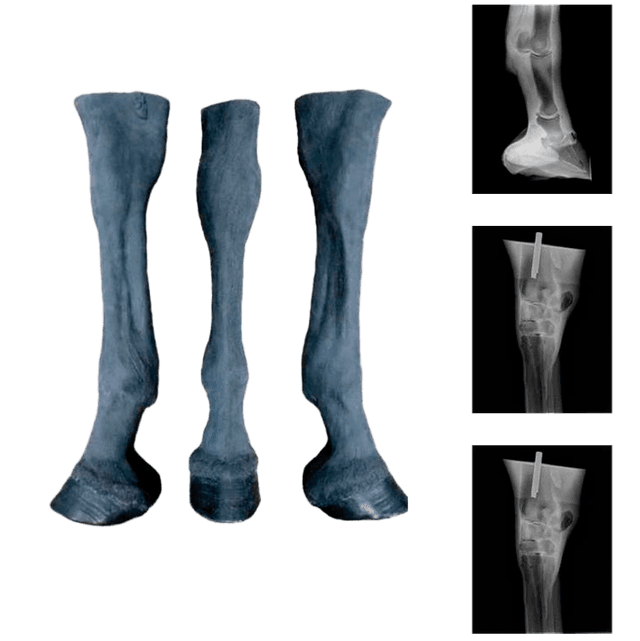

Equino

Encuentra todo lo necesario para el cuidado y rendimiento de tus caballos. En esta categoría descubrirás desde productos para cascos y pezuñas hasta herramientas de establo y material veterinario especializado. Todo lo que necesitas para el cuidado de tus caballos lo encontrarás aquí, en un solo lugar.